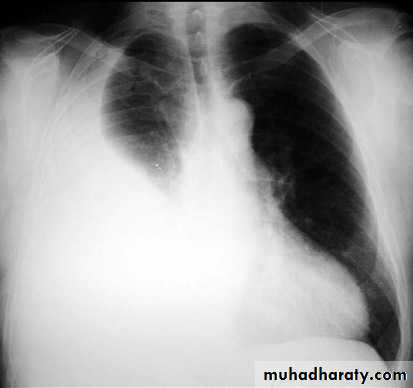

with large volume effusions, mediastinal shift occurs away from the effusion (note: if coexistent collapse dominates then mediastinal shift may occur towards the effusion)

An empyema can resemble a pleural effusion

and can mimic a peripheral pulmonary abscess, although a number of features usually enable distinction between the two Features that help distinguish a pleural effusion from an empyema include:Shape and location

Empyemas usually:

form an obtuse angle with the chest wall

unilateral or markedly asymmetric whereas pleural effusions are (if of any significant size) usually bilateral and similar in size .

lenticular in shape (bi-convex), whereas pleural effusions are crescentic in shape (i.e concave towards the lung)